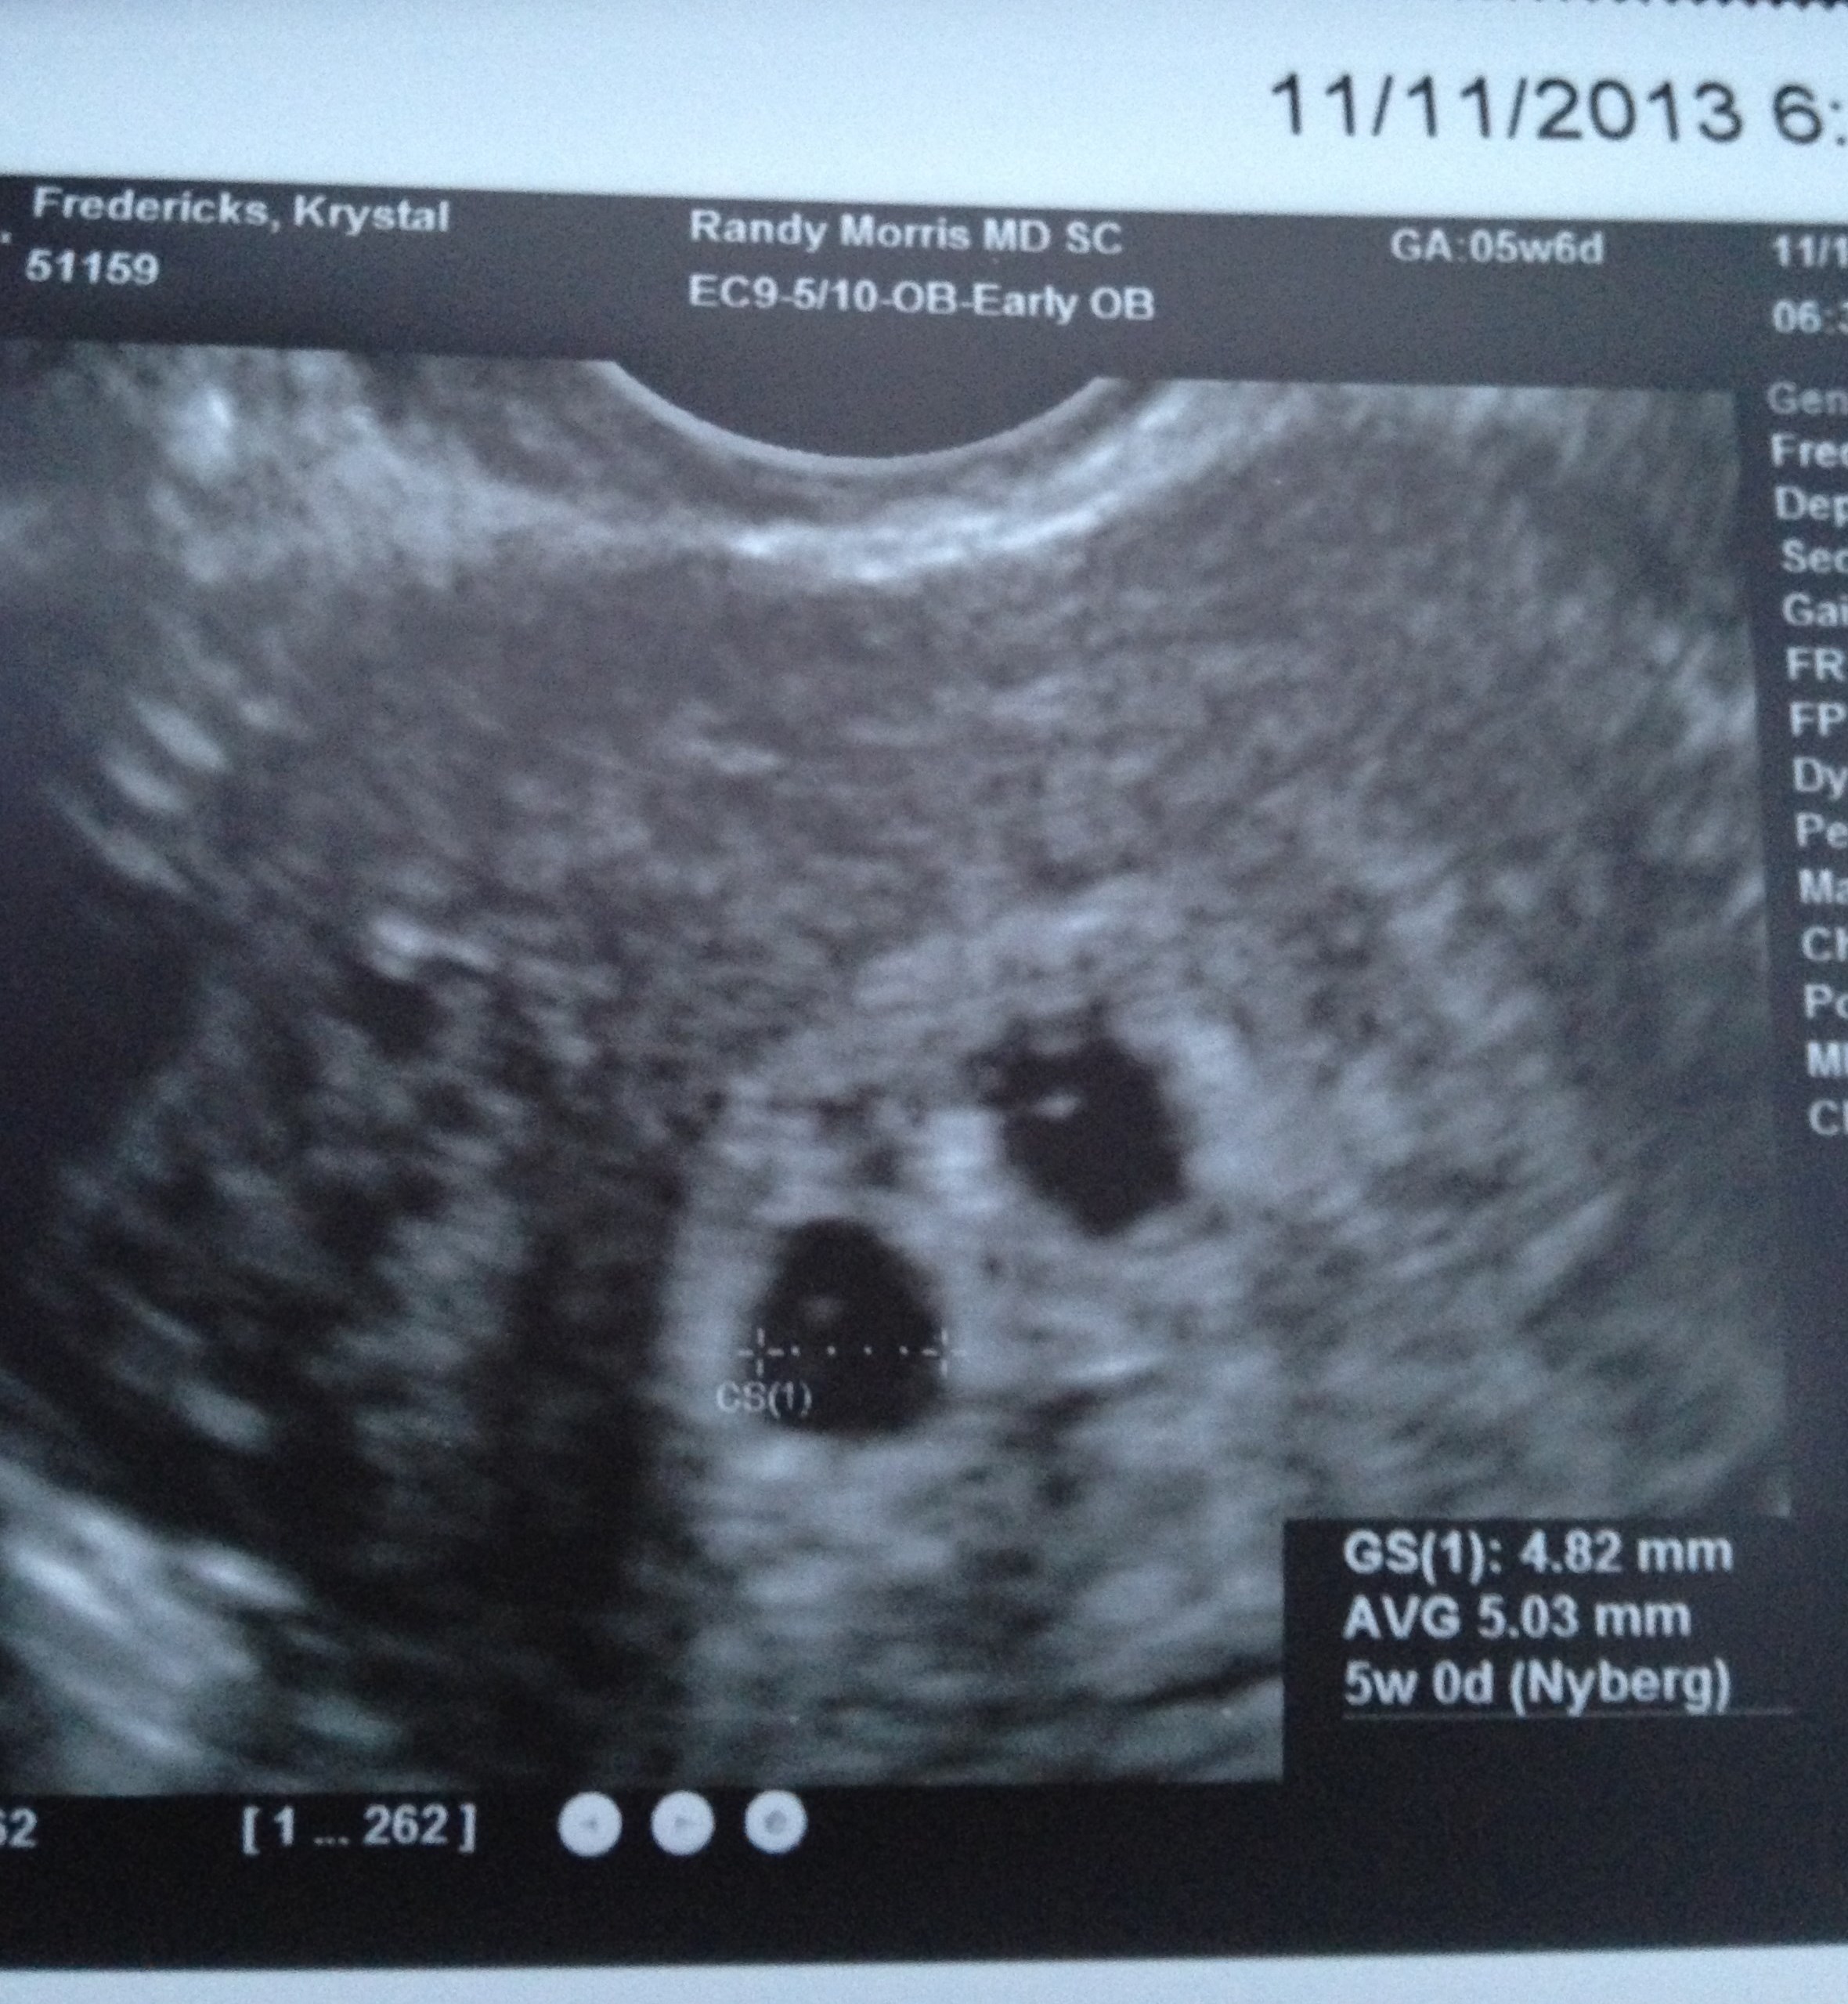

8/13: FET #1 (x1 4AA)=First EVER BFP 4dp5dt!!

d&c @ 6.5 wks, blighted ovum

10/13: FET #2 (x2 4AA)= BFP 4dp5dt! Twins!!, perfect u/s then spontaneous m/c @ 5 wks

Re: 1st u/s (Pic)

U/S 1 @ 6w4d = 1 little frogger with HB of 118, U/S 2 @ 7w3d measuring right on track with HB of 160